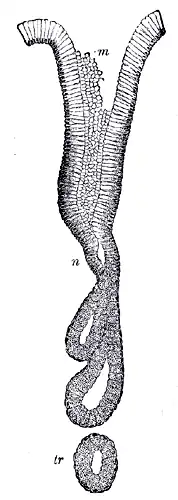

Gastric acid regulation Human pyloric glands (at pylorus)

Human pyloric glands (at pylorus)

The fundic glands (or oxyntic glands), are found in the fundus and body of the stomach. They are simple almost straight tubes, two or more of which open into a single duct. Oxyntic means acid-secreting and they secrete hydrochloric acid (HCl) and intrinsic factor.[7]

The pyloric glands are located in the antrum of the pylorus. They secrete gastrin produced by their G cells.[8]